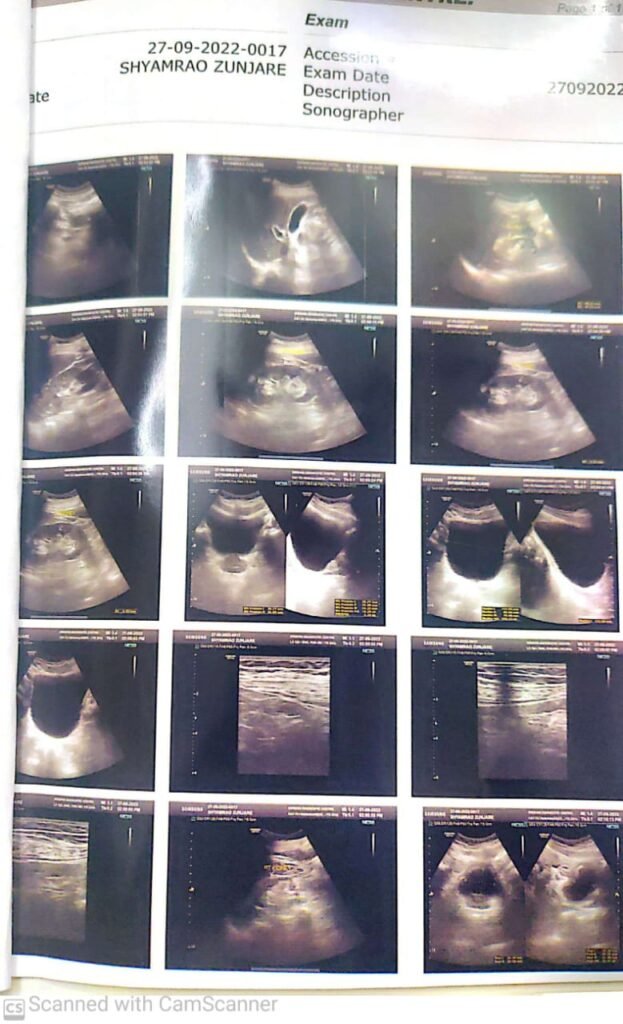

Case Study: Enlargement of Prostate

A case of enlargement of prostate suffer from urine frequency, night urine frequency multiple times comes to normal with our prostate rejuvenation therapy.

The patient was suffering from enlargement of the prostate, experiencing frequent urination during the day and multiple episodes of night-time urination, which affected his sleep and quality of life.